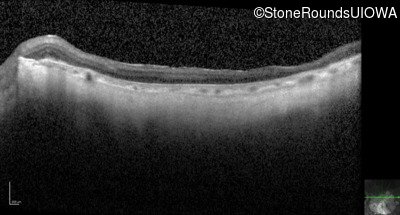

Optical Coherence Tomography - Left - 10/400 sc

Exemplar / OCT Stack

OCT Stack